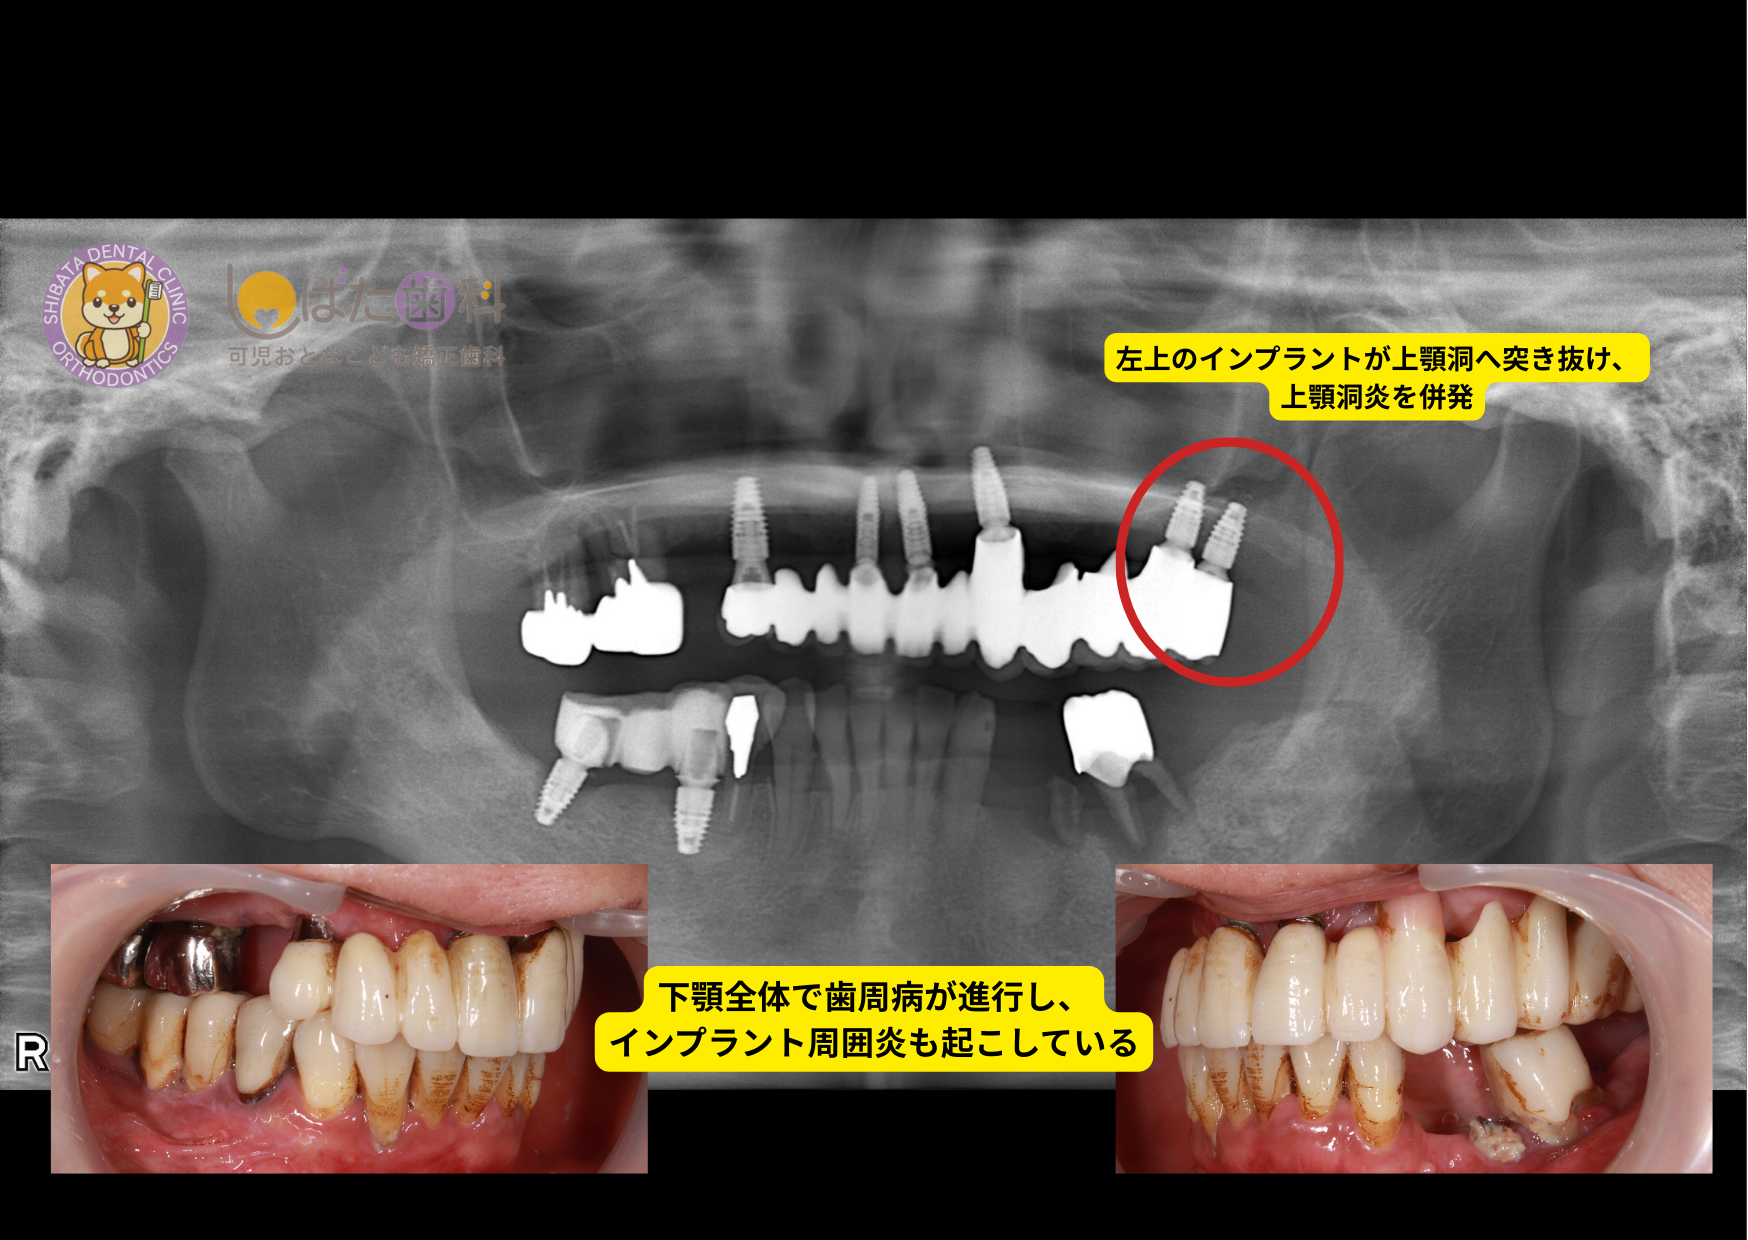

今回ご紹介するもう一つのケースも、費用のみを優先して選択されたことが背景にありました。

50代の女性。

7年前に他院にてインプラント治療を受けられ、その後セカンドオピニオンとして当院に来院されました。

本来、保証や長期的なメンテナンスの観点からも、インプラントを行った医院に継続して通院されることが理想ですが、今回は「主治医の先生が怖く、相談がしづらくなってしまった」との理由から通院が途絶えてしまったそうです。

気になる症状を伝えても「大丈夫」の一言のみ、保証内容について尋ねても具体的な説明が得られず、不安だけが残ってしまったとのこと。

では、なぜその医院で治療を決断されたのか伺ったところ、やはり「費用の安さ」が最大の決め手だったとお話くださいました。

しかし、来院された時にはすでに以下の問題が確認されました。

→その後、当院で撤去を行い、「外してから楽になった」とお話いただきました

これらは、インプラントを入れた後も適切なメンテナンス体制が整っていたり、治療計画や技術面が十分確立されていれば、避けられた可能性が高いものだと考えています。